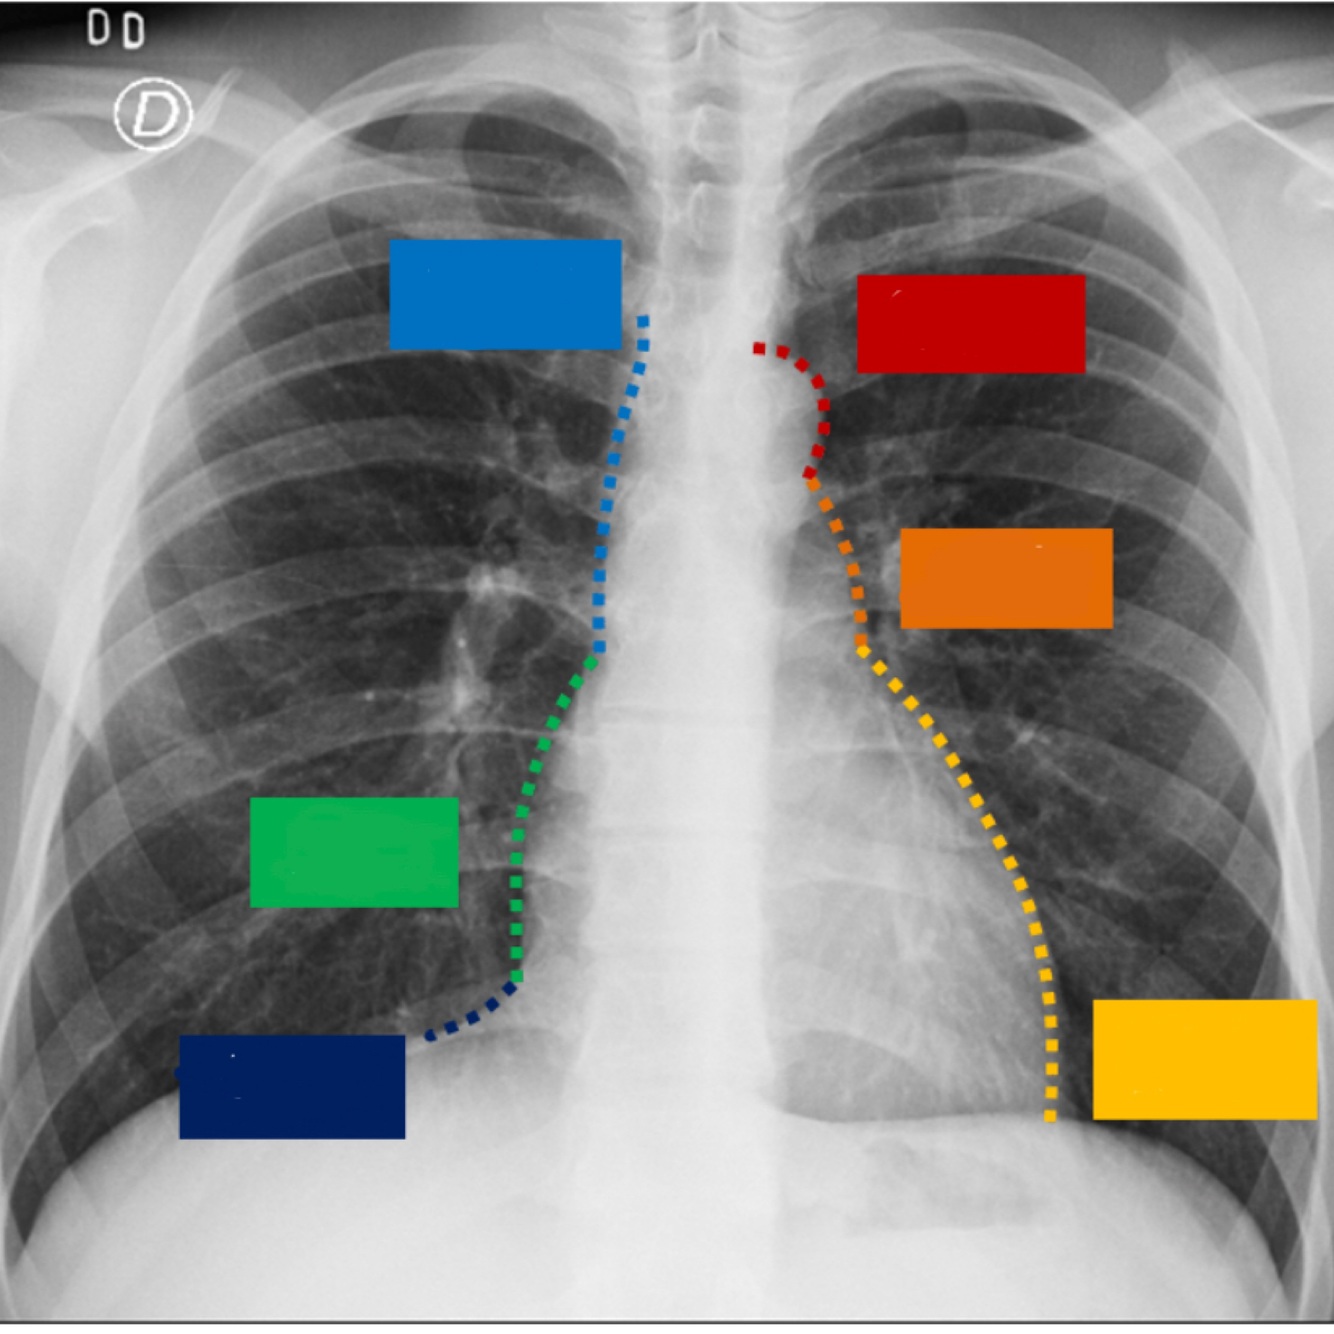

Q

Describe el perfil cardiaco

A